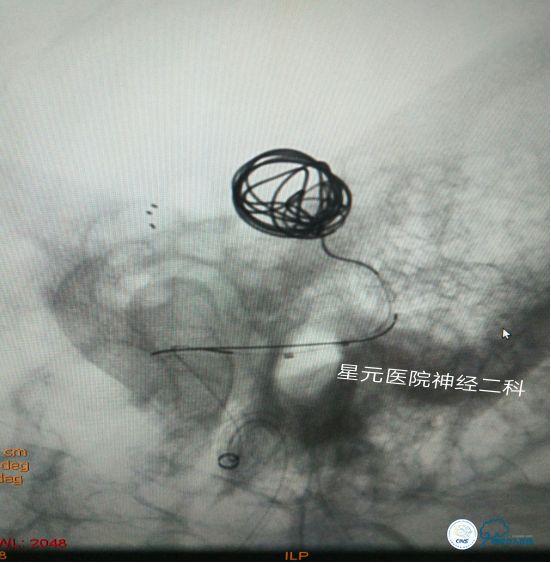

方案一:冰激凌技术(支架托举弹簧圈)

➤用260泥鳅导丝将6F-115 Naviven,通过 8F GUIDING,在路图下缓慢送至颈内动脉海绵窦段,再将Headway17(标记为A)微导管,在0.014 微导丝的引导下通过Naviven超选入动脉瘤体内进行预留。重复上述步骤将另外一根Headway17(标记为B)微导管也超选入并预留到动脉瘤内。根据测量选择Solitaire颅内支架系统引入微导管(A),将支架输送致动脉瘤体中部精准半释放。

➤选用MicroVention 8mm—30cm弹簧圈,通过Headway17(B)缓慢进行瘤体栓塞,反复尝试后发现无法实现预计的弹簧圈托举,弹簧圈总是向瘤体底部盘旋(栓堵住了瘤体底部所发出的侧枝),且有缠绕支架的风险,随之放弃该方案。